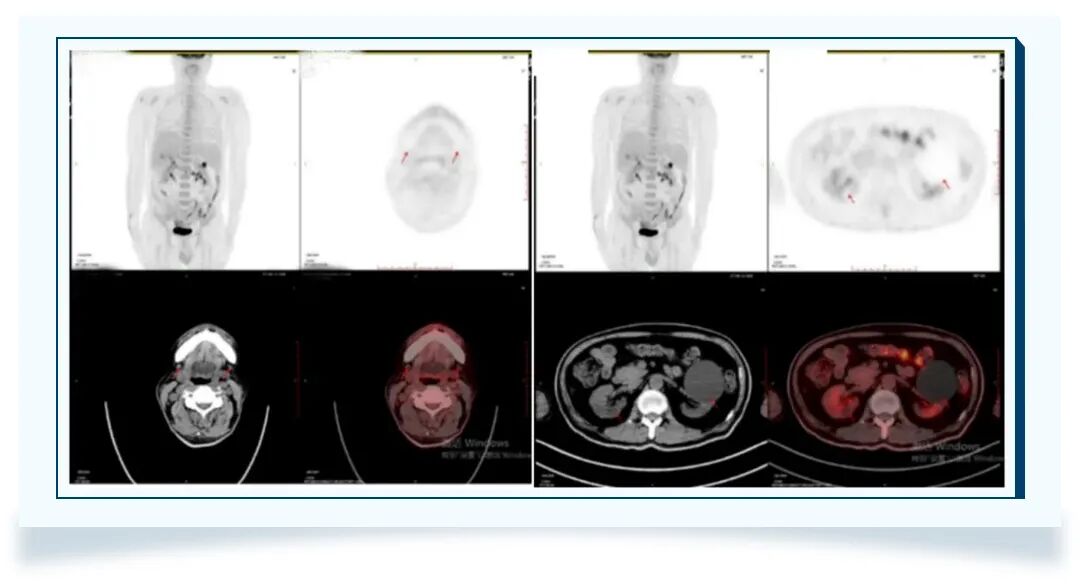

PET-CT(2025-07-11)

1)a.双肺弥漫性FDG代谢增高,同机CT示双肺多发磨玻璃结节、斑片影,双叶上叶为著;b.脾脏及双肾弥漫性FDG代谢稍增高;c.扫描所见中轴骨、骨盆骨及四肢骨近端弥漫性FDG代谢增高;综上影像表现,首先考虑血液系统疾病累及,请结合病理学检查;

2)颅脑FDG代谢及密度未见异常。